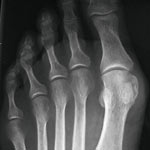

Abb. 3

Hallux-Korrektur